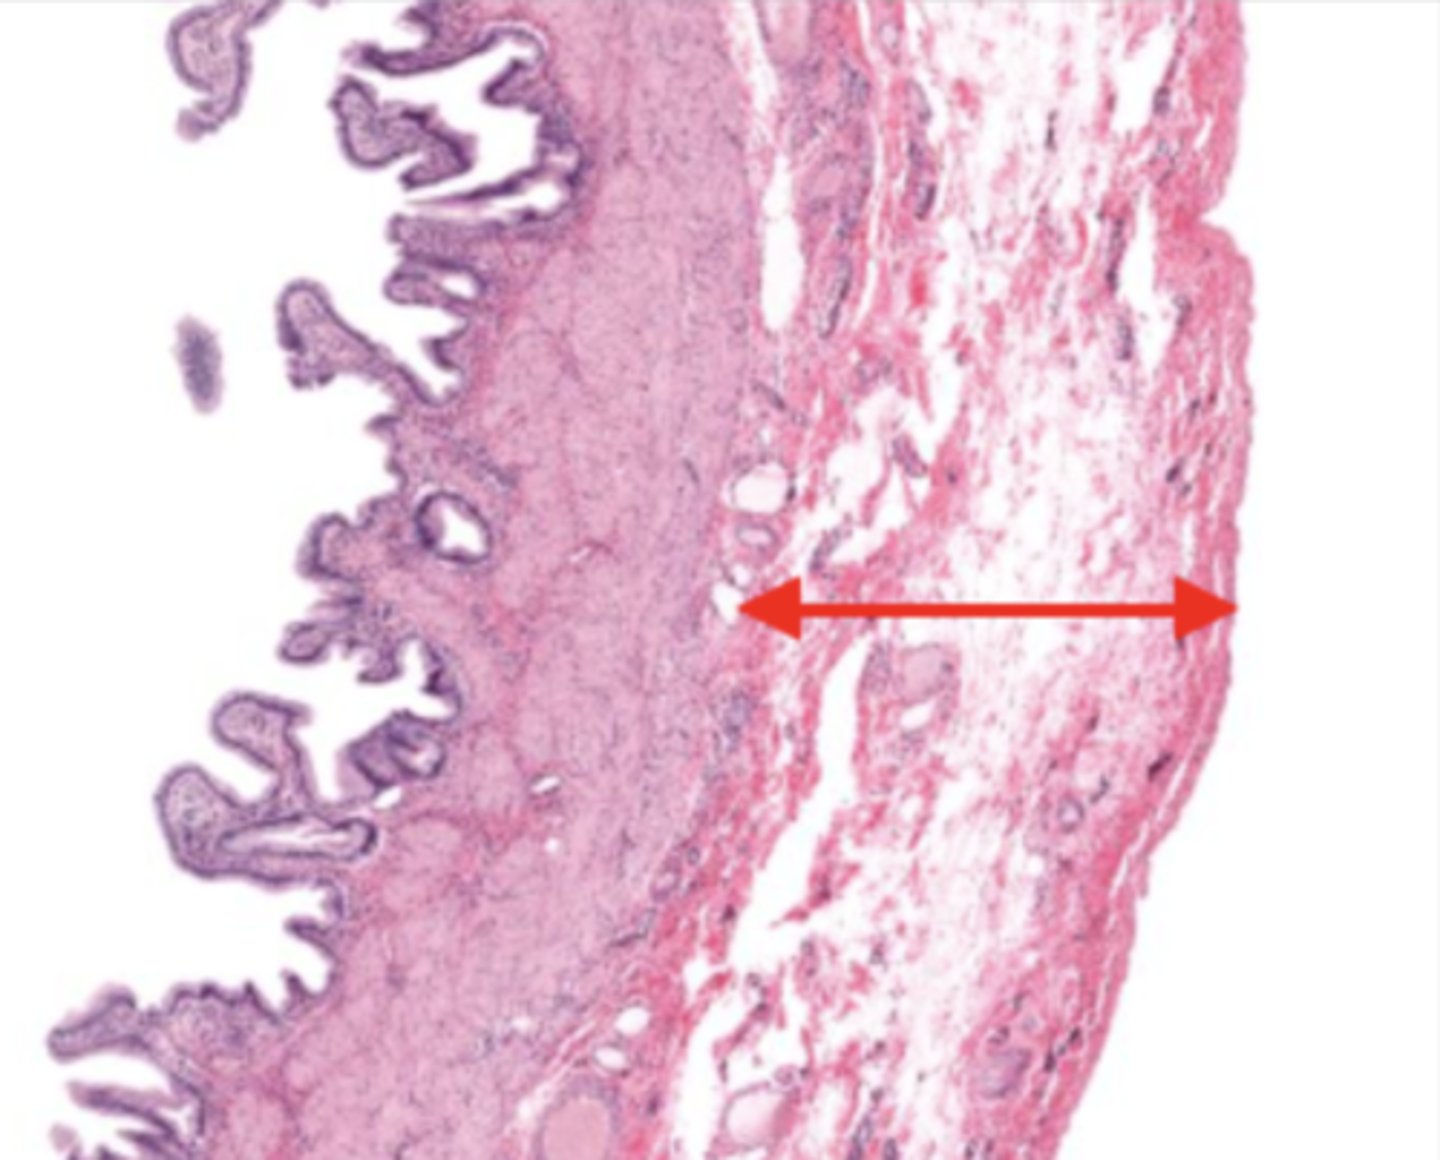

jejunum (histology)

villi (jejunum)

intestinal crypts (jejunum)

lumen (jejunum)

mucosa (jejunum)

mucosal epithelium (jejunum)

lamina propria (jejunum)

muscularis mucosa (jejunum)

submucosa (jejunum)

contains glands and blood supply

muscularis externa (jejunum)

serosa/adventitia (jejunum)